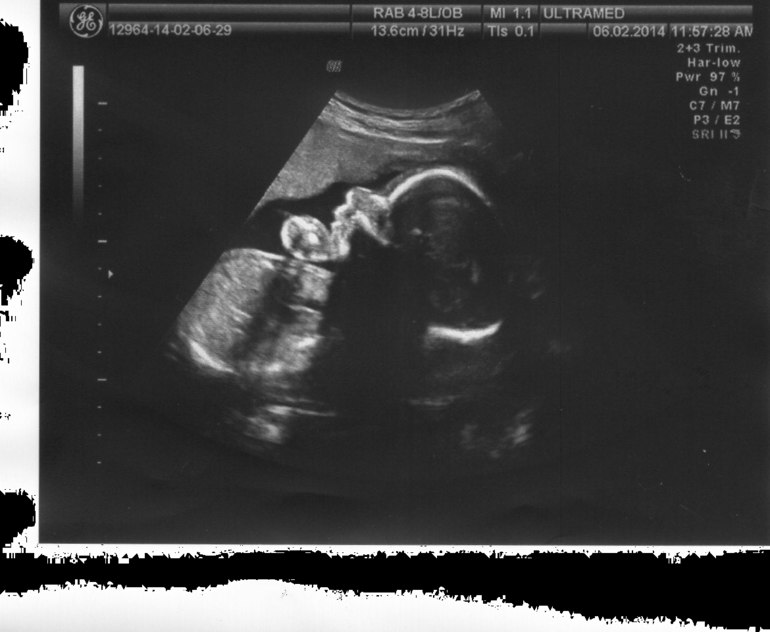

Узи!!!!!!21 нед

УЗИ, КТГ, доплерВот мы и сходили сегодня на наше второе плановое УЗИ.И нам сказали что у нас-->

подтверждается Матвейка))))))я и не сомневалась))))

Весим мы 408 грамм.Срок мой 21+2,а сынок опережает на 1 день,так что ПДР с 17 перенесли на 16.06)))))Младший сыночек опережает нашего первенца на этом сроке на 100 гр веса,но вот косточки покороче на 2-3 мм чем у Данюхи)Будет пухликом)))))Воды в норме,плацента 20 мм как и при первой Б на этом же сроке,зрелось 0. Почки мои в этот раз меня не подвели,в отличии от первой Б,тогда уже была каликоэктазия. Сердцебиение и кровоток в норме. Лежит уже правильно,головкой внизу. Тетя Узист сказала какой хороший малыш,всё то у него как положено!

Ходили мы на 2Д,но тетя врач решила нас немного побаловать и показала Матвейку и в 3Д